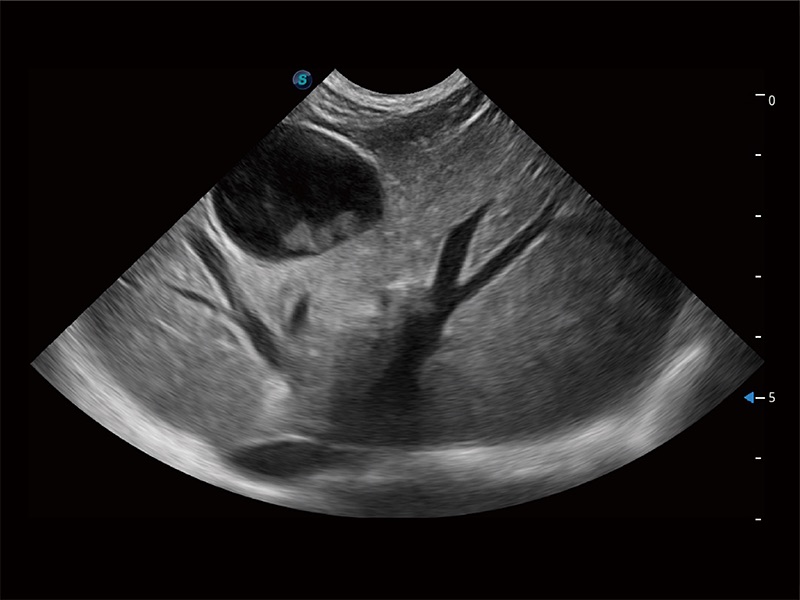

(犬)胎儿主动脉弓立体血流

(犬)胎儿四腔心